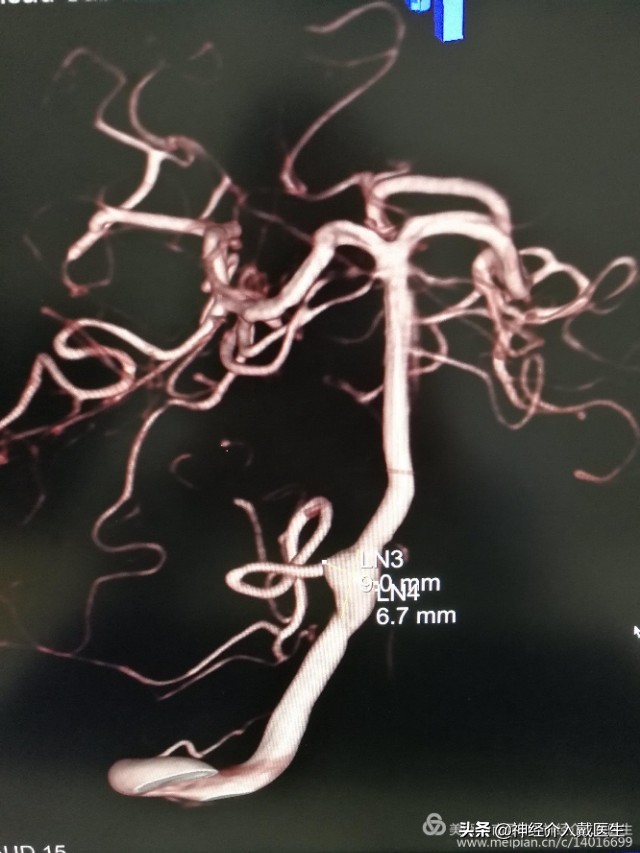

脑血管造影显示右侧椎动脉V4段动脉瘤,并且是比较少见的夹层动脉瘤。长度大约9mm,动脉瘤破口与右侧椎动脉重要分支右侧小脑后下动脉很近。

动脉瘤手术经典治疗方式有开颅夹闭术和介入栓塞术,该动脉瘤位于后循环,后颅窝,脑干附近,显露困难,并且是夹层动脉瘤,开颅夹闭术不合适,介入栓塞术是最好的选择,该动脉瘤位于椎动脉重要分支右侧小脑后下动脉开口处,所以保护右侧小脑后下动脉是手术的重中之重。仔细观看3D,动脉瘤破口与右侧小脑后下动脉开口还是有一定的距离,又是破裂动脉瘤,支架加弹簧圈栓塞是最好的选择,必要时可以用微导管或者支架保护右侧小脑后下动脉。